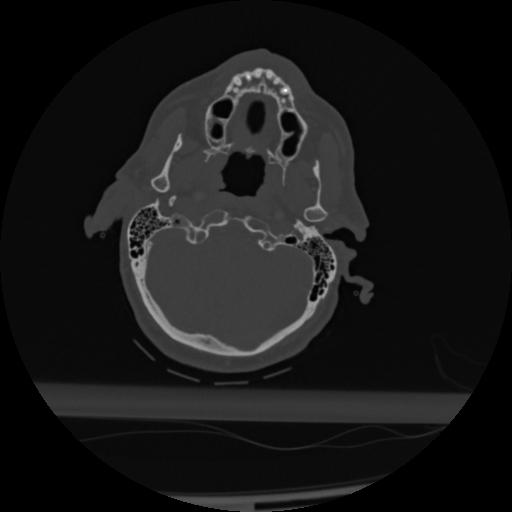

22 ANGIO,CE,Vol,0.5,ANGIO,,